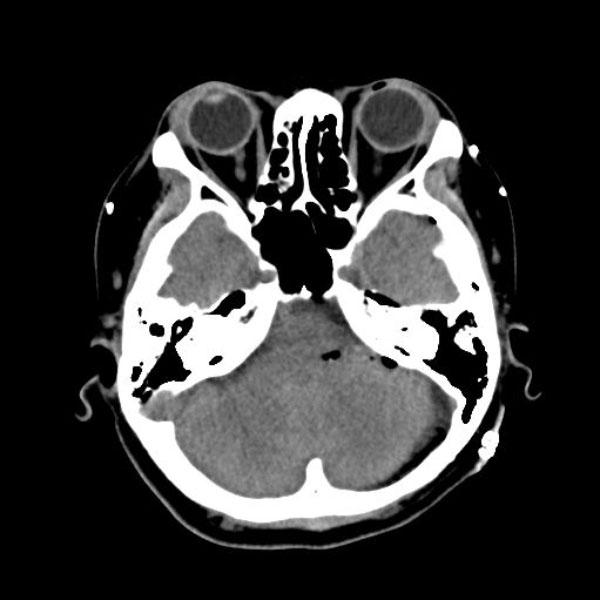

581

大阪府の病院

'26年3月

40代

左顔面痙攣

手術前

減圧前

減圧後

術後血管撮影